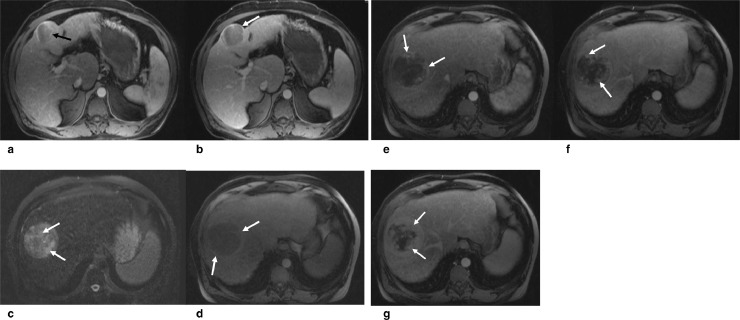

Fig. 2.

(a and b) Dynamic contrast enhanced MRI of the same patient shows a 5.8 cm partially exophytic mass in the segment 4B with mild hyperenhancement on arterial phase (a, arrow), and subsequent washout and rim enhancing capsule (arrow in b) on equilibrium phase, consistent with an OPTN class 5 HCC. (c, d, e, f, g) Dynamic contrast-enhanced MRI of the second lesion in segment 7/8 shows mildly increased but heterogeneous T2 signal intensity (c, arrows) and mildly hyperintense rim on precontrast T1-weighted image (d, arrows). Postcontrast images show a nodular discontinuous peripheral enhancement in the arterial phase (e, arrow) with subsequent progressive inward enhancement in the equilibrium and delayed images (f and g, arrows). Delayed enhancing capsule can be clearly seen in figure g.